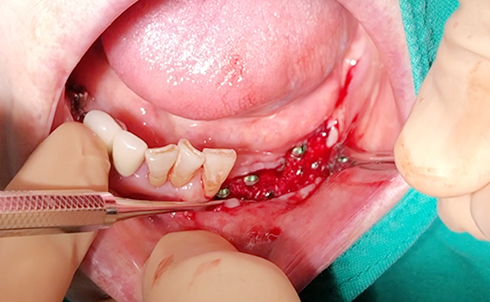

Simultaenous bone grafting for implants

Simultaneous bone graft and implant placement